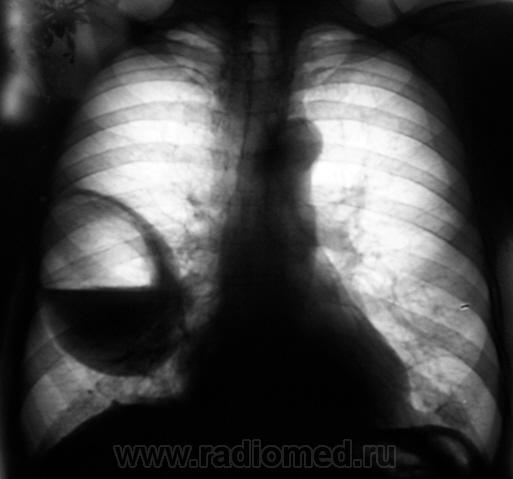

Лаборант «с флюорографа» пригласил посмотреть произведенную флюорограмму.

Лаборант «с флюорографа» пригласил посмотреть произведенную флюорограмму.роизвели рентген

Произвели рентгенографию в стандартных проекциях.

Флюорограмма 2009 года.

сильно похоже на нагноившуюся кисту...

Она и есть.

Но, пациент жалоб не предъявляет...

Значит не нагноившаяся...

Киста, точно киста. Был пациент на консультации у торакальщиков, будут готовить к плановой операции.

Клиника при блокированом абсцессе, а таковой и будет нагноившаяся киста - может быть весьма скудной; при "конкретном" допросе что то и выясниться...а если еще и промониторить пару дней, то нароется куча всего, что вполне и подойдет под такую штуку....Знаем мы их жалобы...типа - "у меня легкие"...."у меня желудок"...сто потов сойдет, пока рациональное ключевое слово не услышишь.